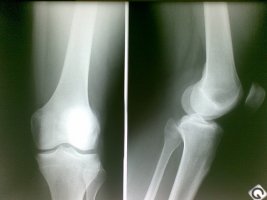

무릎연골연화증

남성들보다는 여성들에게 나타난다는 무릎연골연화증은 무릎아래에 위치한 연골이 약해져서 통증이 발생하여 생기는 질환으로 일반적으로 50대이후인 중 장년층에서 발생하는 것으로 알려져 있지만

있는데요~ 다리가 휘어져 있는 경우 발병률이 높게 나타나며 관절염에서 무릎연골연화증으로 이어지는 경우도 있습니다 무릎연골연화증의 대표적인 증상으로는 무릎이 뻐근한 통증인데요~ 오랜 시간 앉아있다